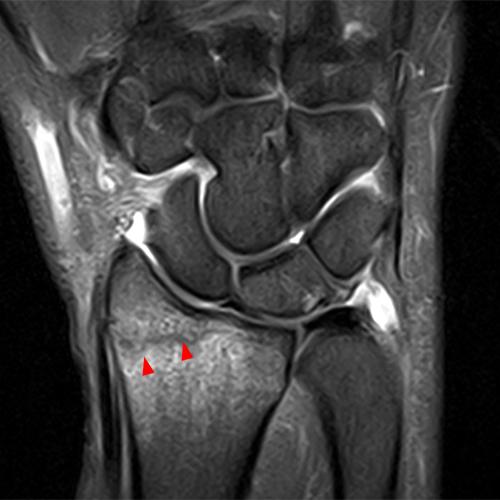

Clinical History: A 68-year-old female presents with radial-sided pain and swelling. Axial T1-weighted (1A), axial fat-suppressed proton density-weighted (1B), and coronal fat-suppressed proton density-weighted (1C) images are provided. What are the findings? What is your diagnosis?

Figure 2: The axial T1-weighted (2A), axial fat-suppressed proton density-weighted (2B), and coronal fat-suppressed proton density-weighted (2C) images demonstrate a thickened extensor retinaculum, surrounding soft tissue edema, and fluid signal in the first extensor compartment of the wrist (arrowheads). Marrow edema is noted within the subjacent radius (asterisks). A single extensor pollicis brevis and two abductor pollicis longus tendon slips are present with heterogeneous intrinsic signal.